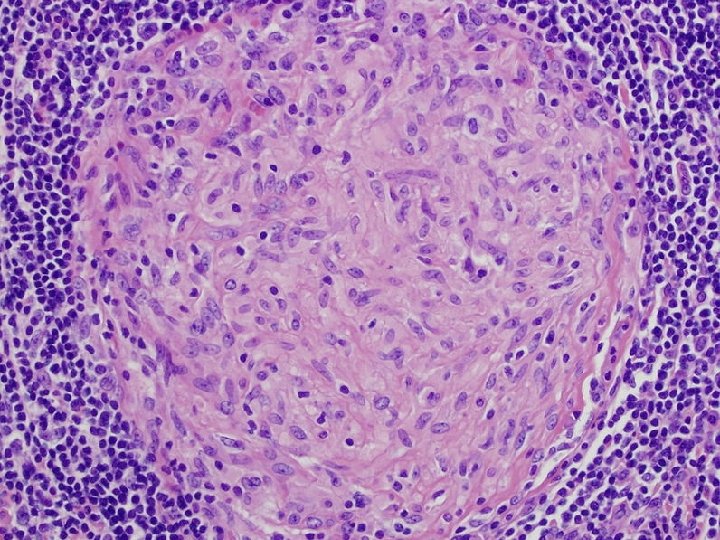

INTRACELLULAR PATHOGENS AND GRANULOMA FORMATION * Mycobacteria can resist killing by activated macrophages resulting in formation of granulomas * Granulomas * Localized inflammatory response characterized by * Central core of infected macrophages surrounded by activated T cell * Central core of granuloma * Macrophages fused into multinucleated giant cells surrounded by large single macrophages (epithelioid cells) * In tuberculosis, centers of large granulomas display cheeselike appearance * Caseation necrosis